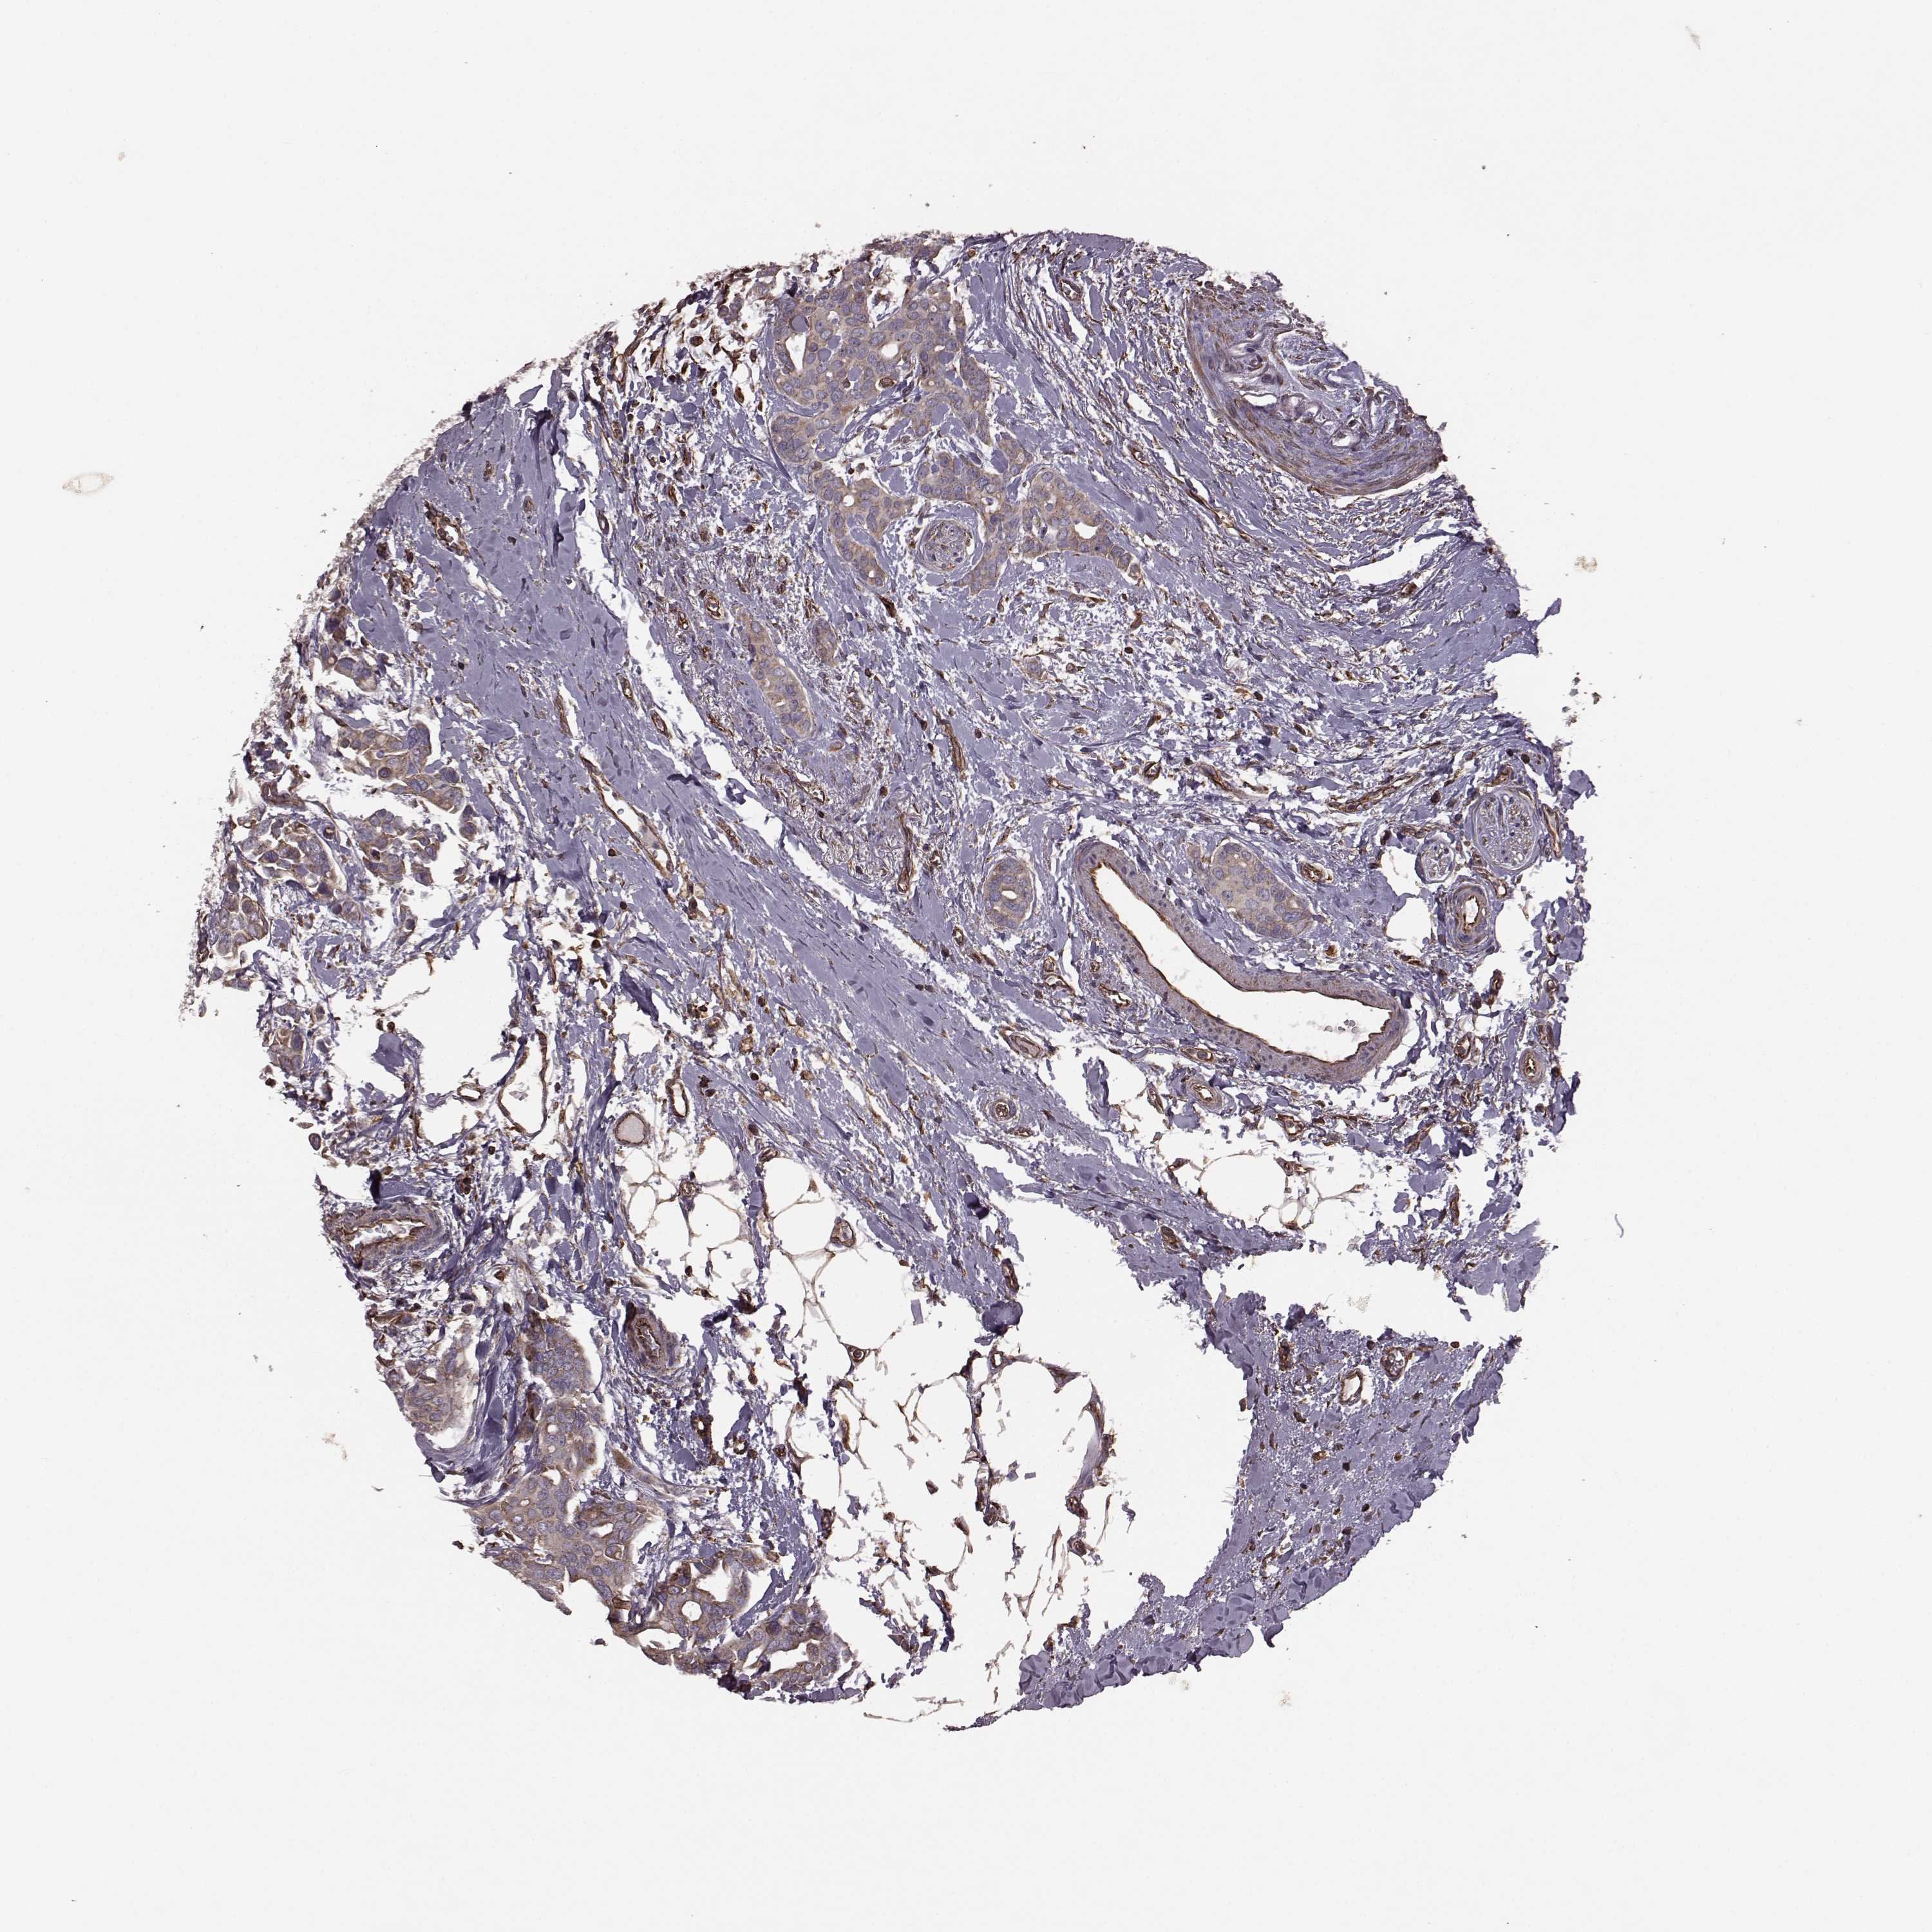

CANCER BREAST CANCER Show tissue menu

BRCA TCGA BRCA VALIDATION PROTEIN EXPRESSION